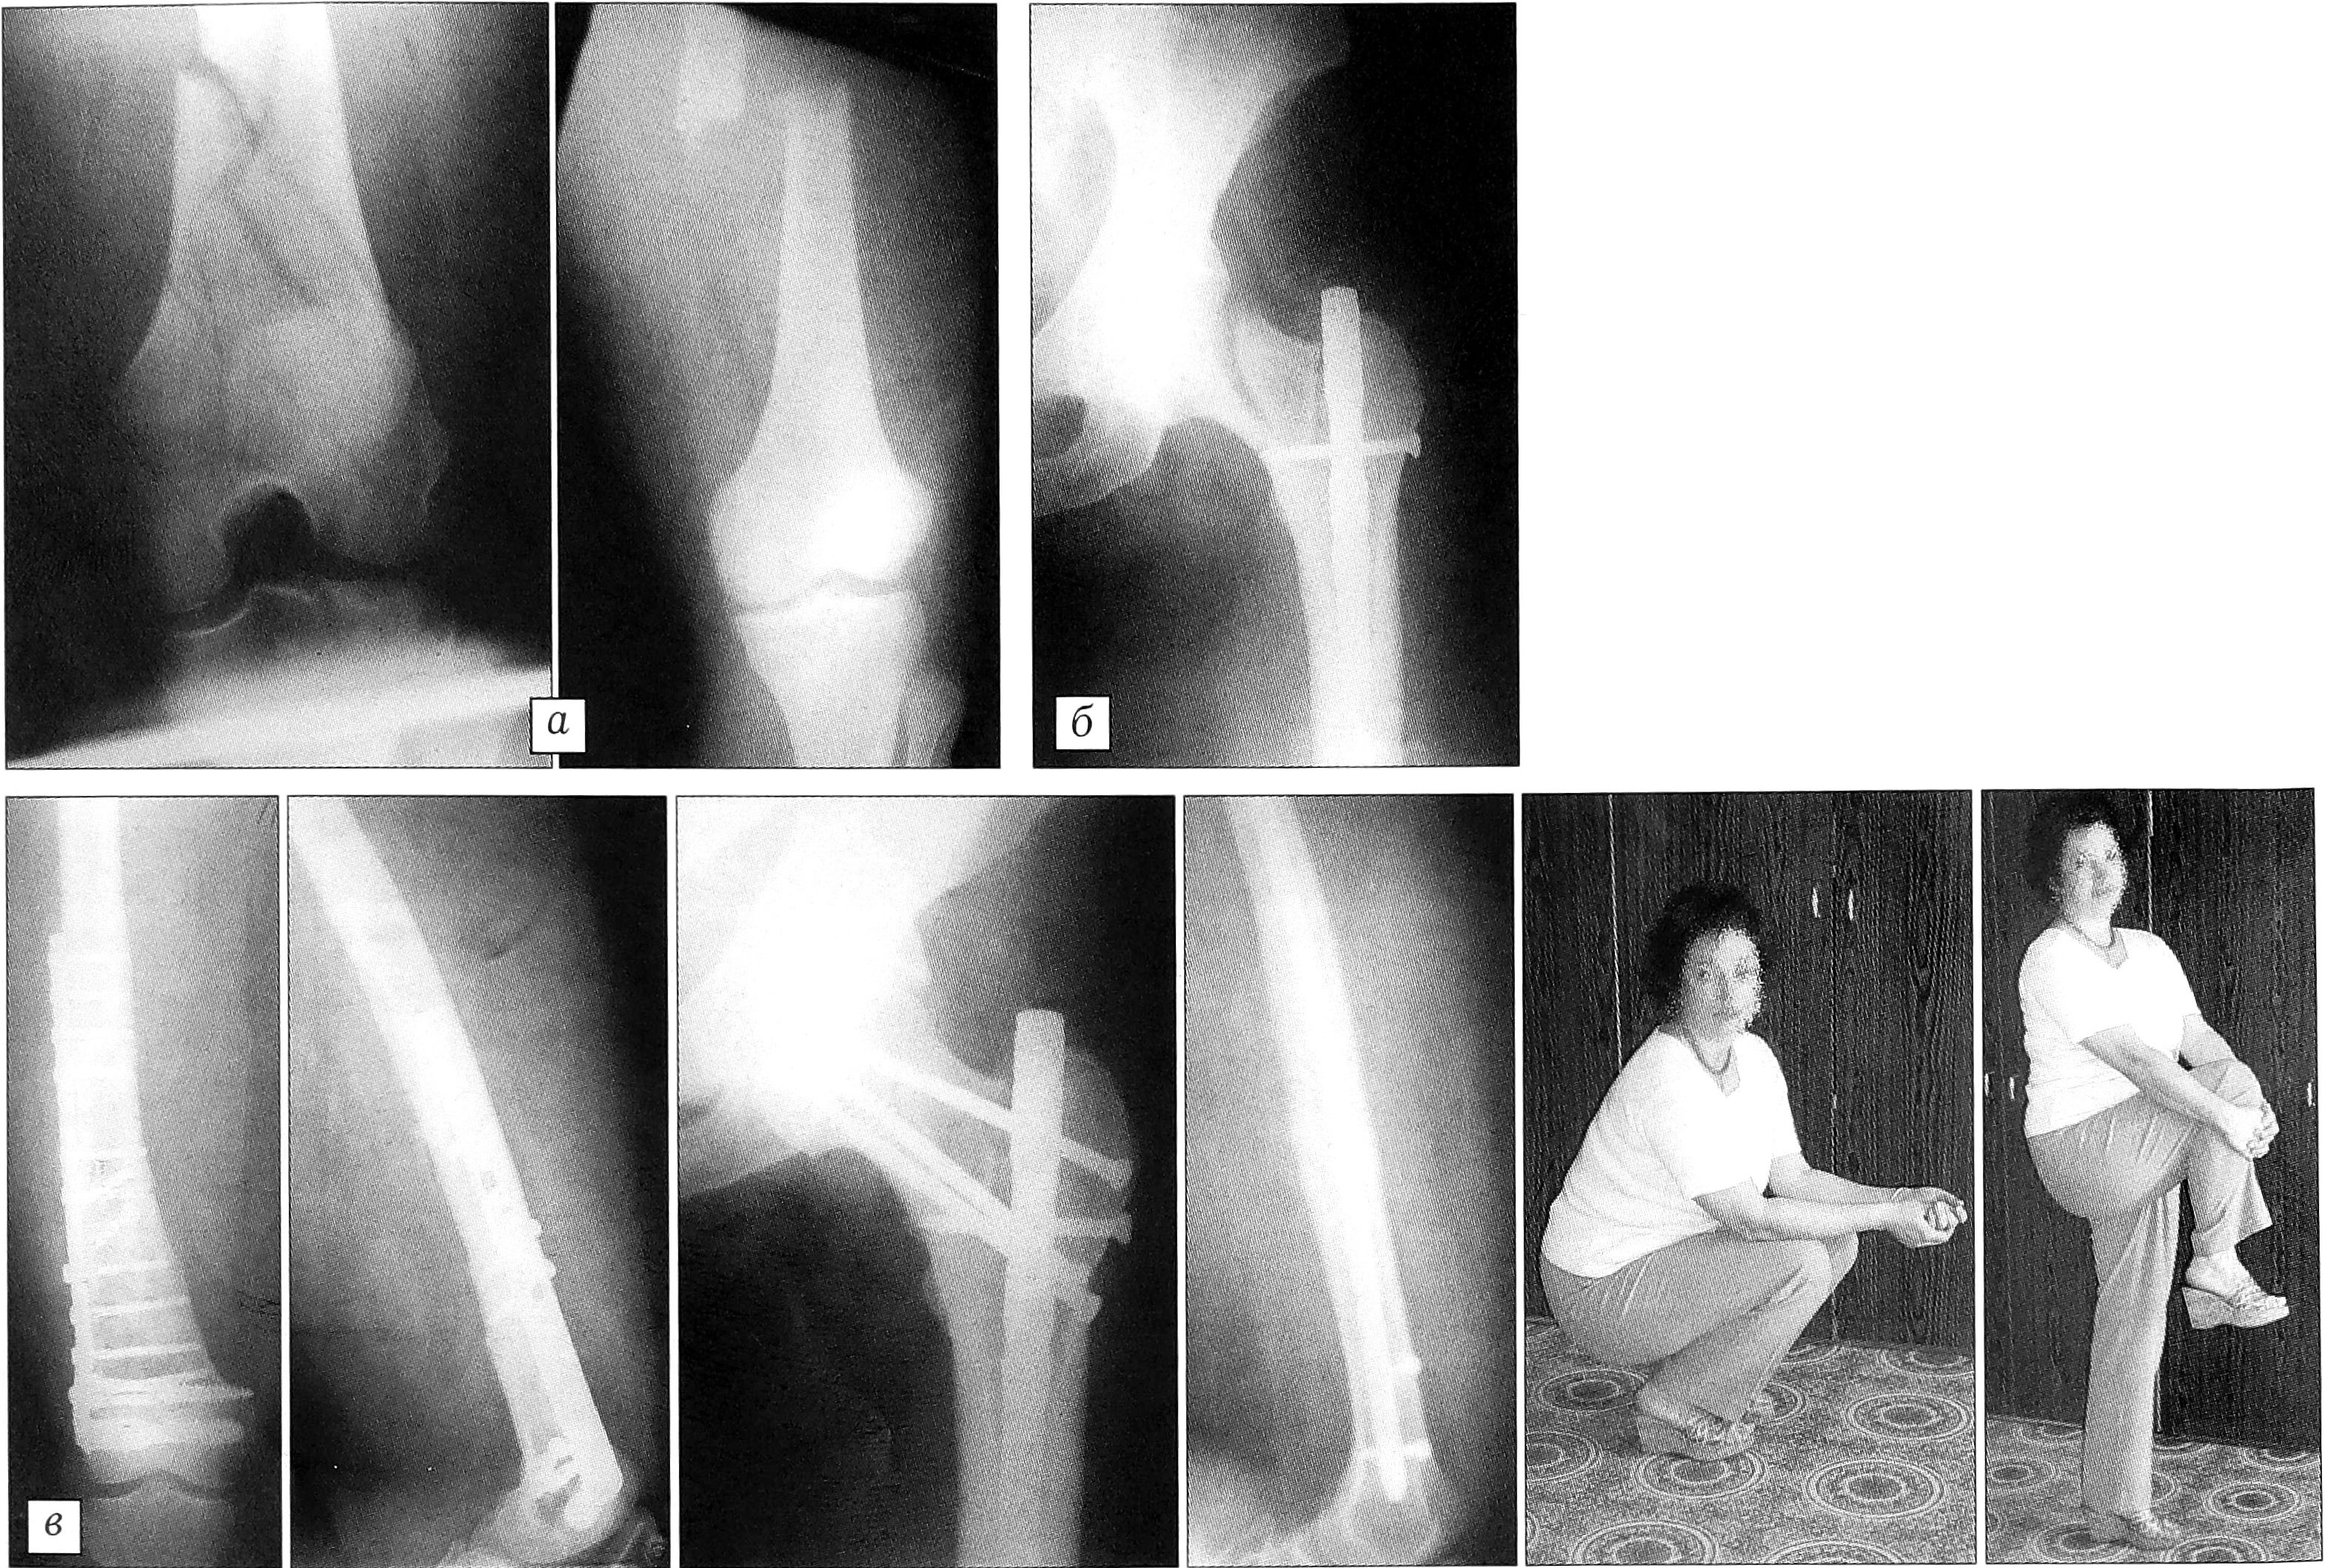

Пример. Больная Г.,38 лет, поступила в клинику 26.07.00. Травма получена в результате падения с высоты 4-го этажа. При поступлении диагностированы закрытый многооскольчатый внутрисуставной перелом дистального отдела правого бедра, закрытый оскольчатый перелом средней трети левого бедра (рис. 2, а). Обе нижние конечности иммобилизованы скелетным вытяжением за проксимальные метафизы большеберцовых костей. После проведения противошоковой терапии на 2-е сутки одномоментно последовательно выполнены открытая репозиция и остеосинтез правого бедра фиксатором DCS; закрытая репозиция и блокирующий остеосинтез левого бедра стержнем UFN. Во время второй операции на ЭОП выявлен перелом шейки левого бедра (рис. 2, б). Ранее была допущена диагностическая ошибка: при поступлении больной не произведена рентгенография левого тазобедренного сустава. В этом же наркозе последовательно выполнен остеосинтез шейки бедра тремя винтами. Послеоперационный период протекал без осложнений. Полная нагрузка на обе нижние конечности разрешена через 4 мес. Пациентка осмотрена через 1 год: полное функциональное восстановление (рис. 2, в).

Рис. 2. Больная Г. 38 лет. Закрытый многооскольчатый внутрисуставной перелом дистального отдела правого бедра, оскольчатый перелом средней трети левого бедра. а — рентгенограммы при поступлении; б — интраоперационная рентгенограмма левого бедра; выявлен абдукционный перелом шейки; в — рентгенограммыифункциональный результат через 1 год.